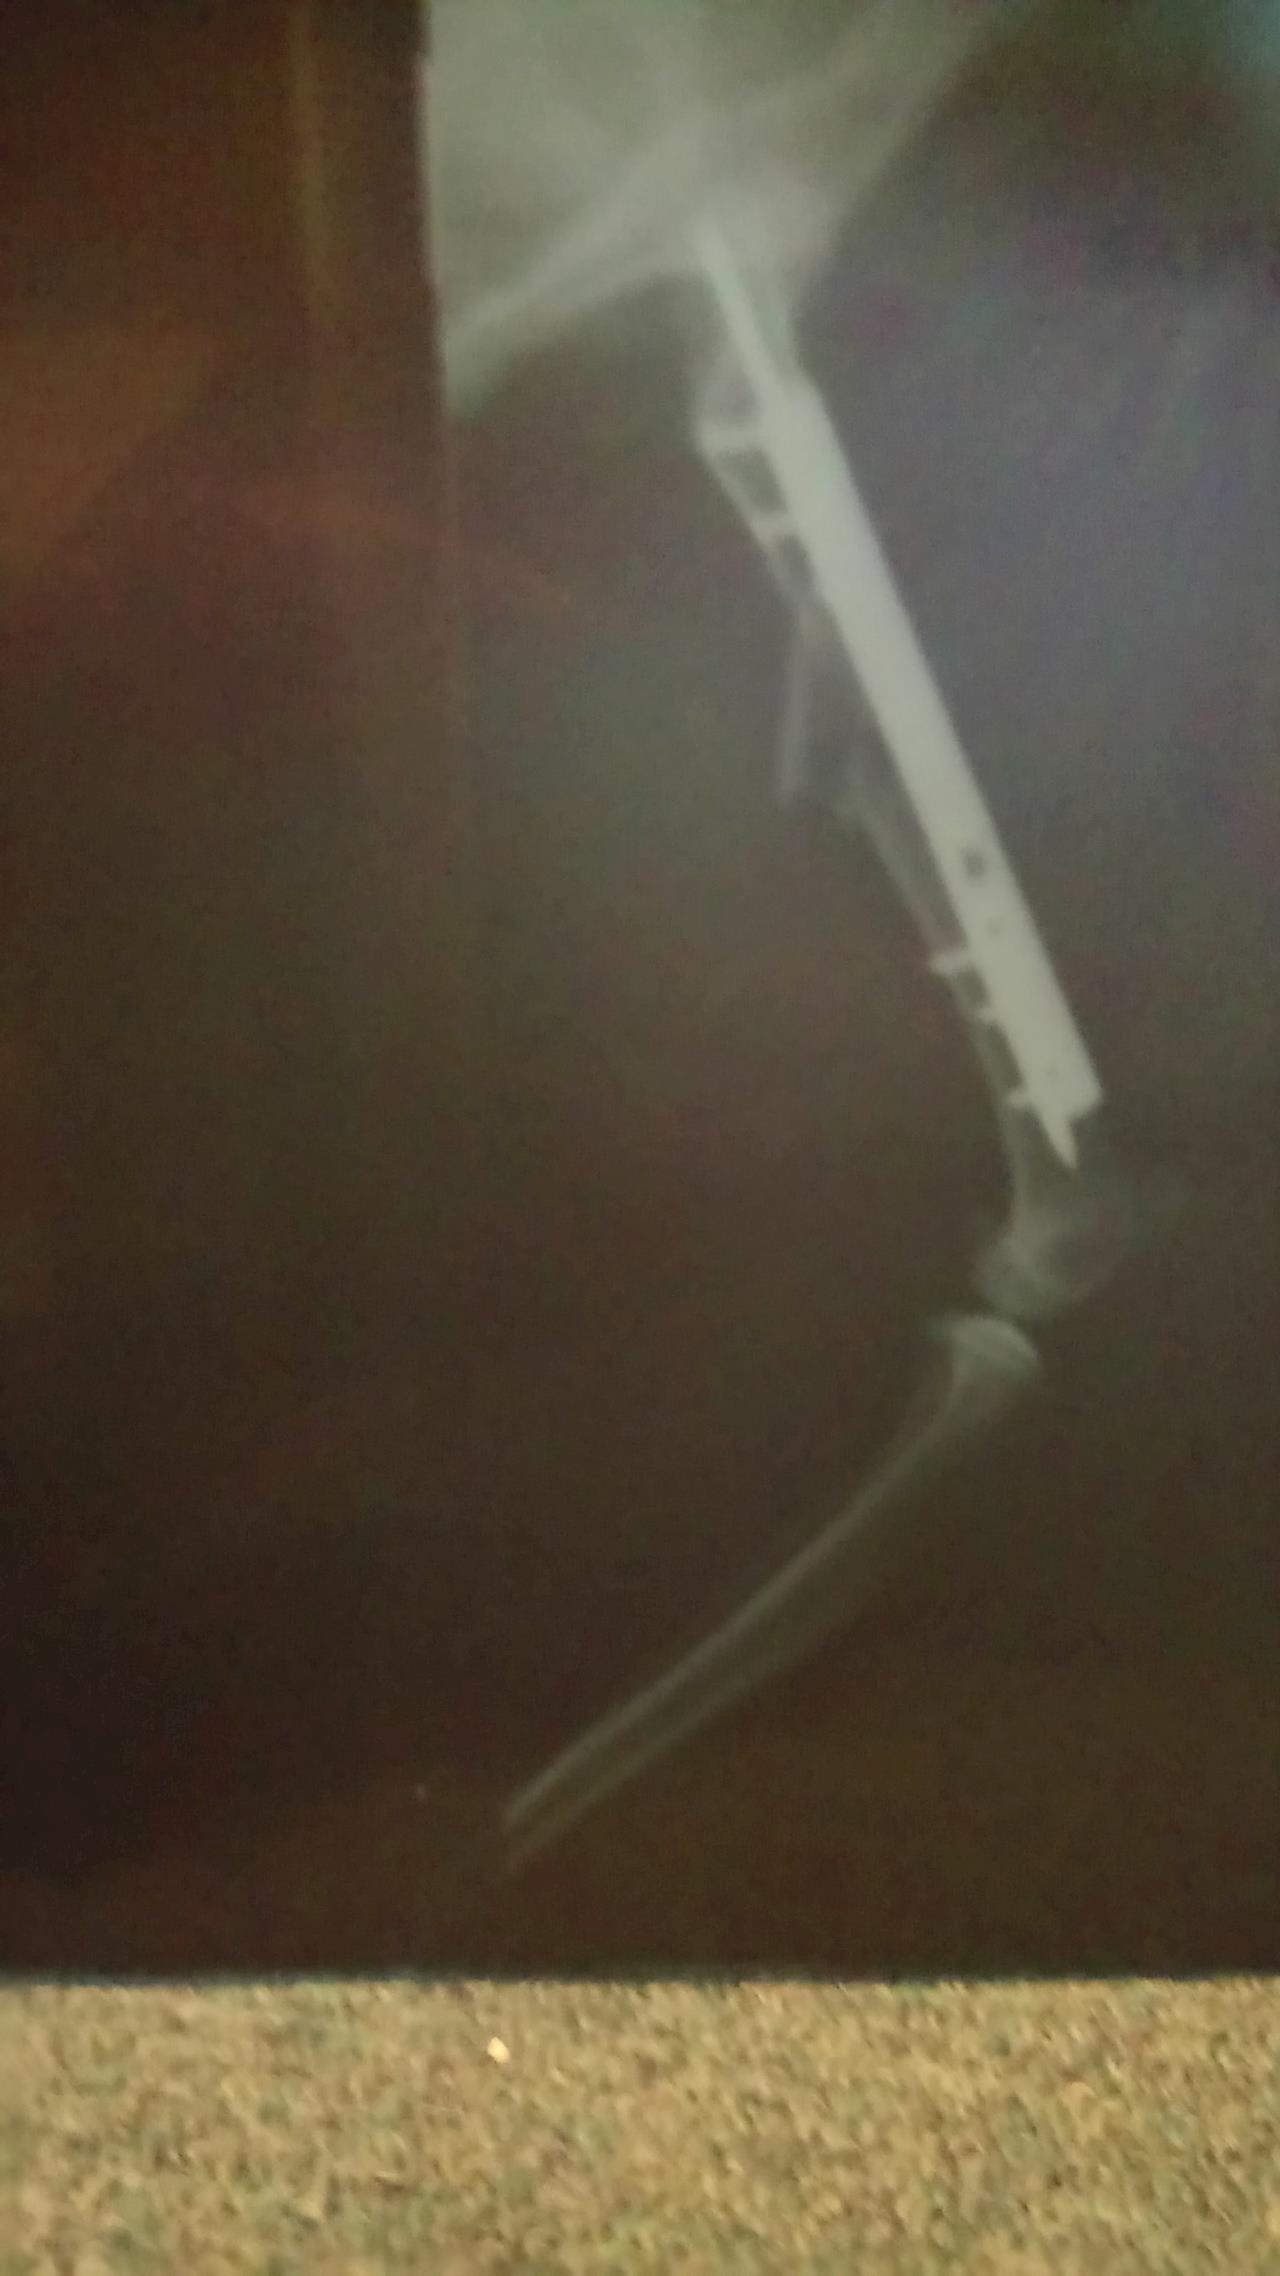

Xrays after the operation  30 August 2017

So here you can see the Rod they inserted into the middle of the bone and attached plates and screws to hold the bone in place.